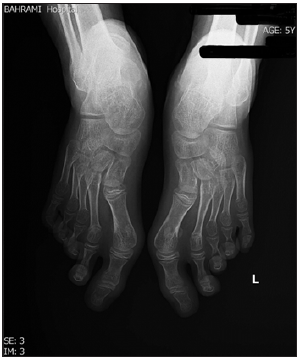

A 5-year-old girl was admitted to the Rheumatology Ward of Bahrami Children’s Hospital affiliated with Tehran University of Medical Sciences with prolonged hallux valgus since one year ago and pain in the first toe (Figure 1). Family and drug history were negative. Her weight and height were 30kg and 135cm, which were above the 95th percentile for age. Physical examination showed generalized hyperpigmentation, hallux valgus, and lateral deviation of hand fingers. The patient was in the pre-pubertal stage .The accelerated growth rate along with skeletal deformity and hyperpigmentation raised suspicion for an endocrine disturbance .Therefore, endocrine consultation was requested to evaluate the adrenal function by measuring ACTH, cortisol, TSH (Thyroid-Stimulating Hormone), and 25 (OH) vitamin D. The cortisol level was lower than normal while the ACTH level was well above the normal limits .Laboratory findings are summarized in Table 1. A hands and feet X-ray showed decreased density of the metacarpal bones as well as lateral deviation of the fingers (bone age=9 years and 6 months) (Figures 2 & 3). Whole exome sequencing revealed homozygous mutation of MC2R gene. The diagnosis was made and she was treated with hydrocortisone [3,4]. She was followed up by a pediatrician and her growth rate, ACTH, and FBS (Fasting Blood Sugar) were observed.

Figure 2:Bilateral Feet-Xray of the case.